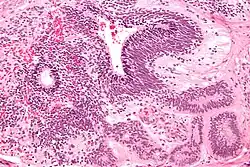

The ovarian yolk sac tumors, also known as endodermal sinus tumors, are accountable for approximately 15.5% of all OGCTs.[8] They have been observed in women particularly in their early ages, and rarely after 40 years of age.[9] The critical pathologic features are a smooth external surface and capsular tears due to their rapid rate of growth. A study consisting of 71 individual cases of ovarian yolk sac tumor provides evidence to the proliferation of the tumor. In one of the cases, the pelvic examination revealed normal activity until a 9 cm and 12 cm sized tumor was discovered 4 weeks later.[9] In another case, a 23 cm tumor was discovered in a pregnant woman who was monitored regularly and had normal findings until oophorectomy became essential.[9] Histologically, these tumors are characterized by mixed solid and cystic components.[1] The mixed solid components are characterized by a soft gray to yellow solid components accompanied with significant hemorrhage and necrosis. The cysts are approximately 2 cm in diameter and populated throughout the tissue which results in giving the neoplasm a ‘honeycombed appearance’.[1]